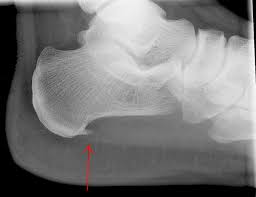

X-Ray

If the preliminary examination suggests calcaneal spur, then your doctor can order an x-ray. The x-ray images can reveal the growth in your heel bone.